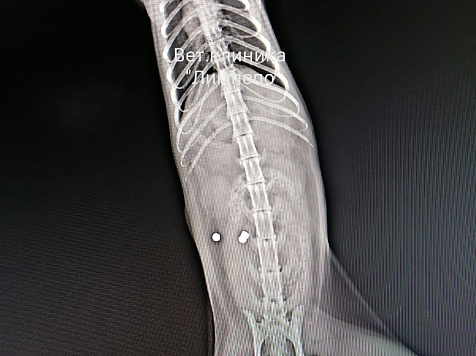

Животное с семью пулями в теле лечат в ветклинике «Лимпопо»

Сотрудники городской полиции проводят проверку по факту травмирования животного. Как рассказал «7 канал Красноярск» накануне, клиника «Лимпопо» опубликовала рентгеновские снимки животные, на которых хорошо видно, что в теле застряли семь пуль. В комментариях люди вспоминают и другие случаи жестокого обращения с питомцами и требуют ужесточения наказания за подобные проступки.